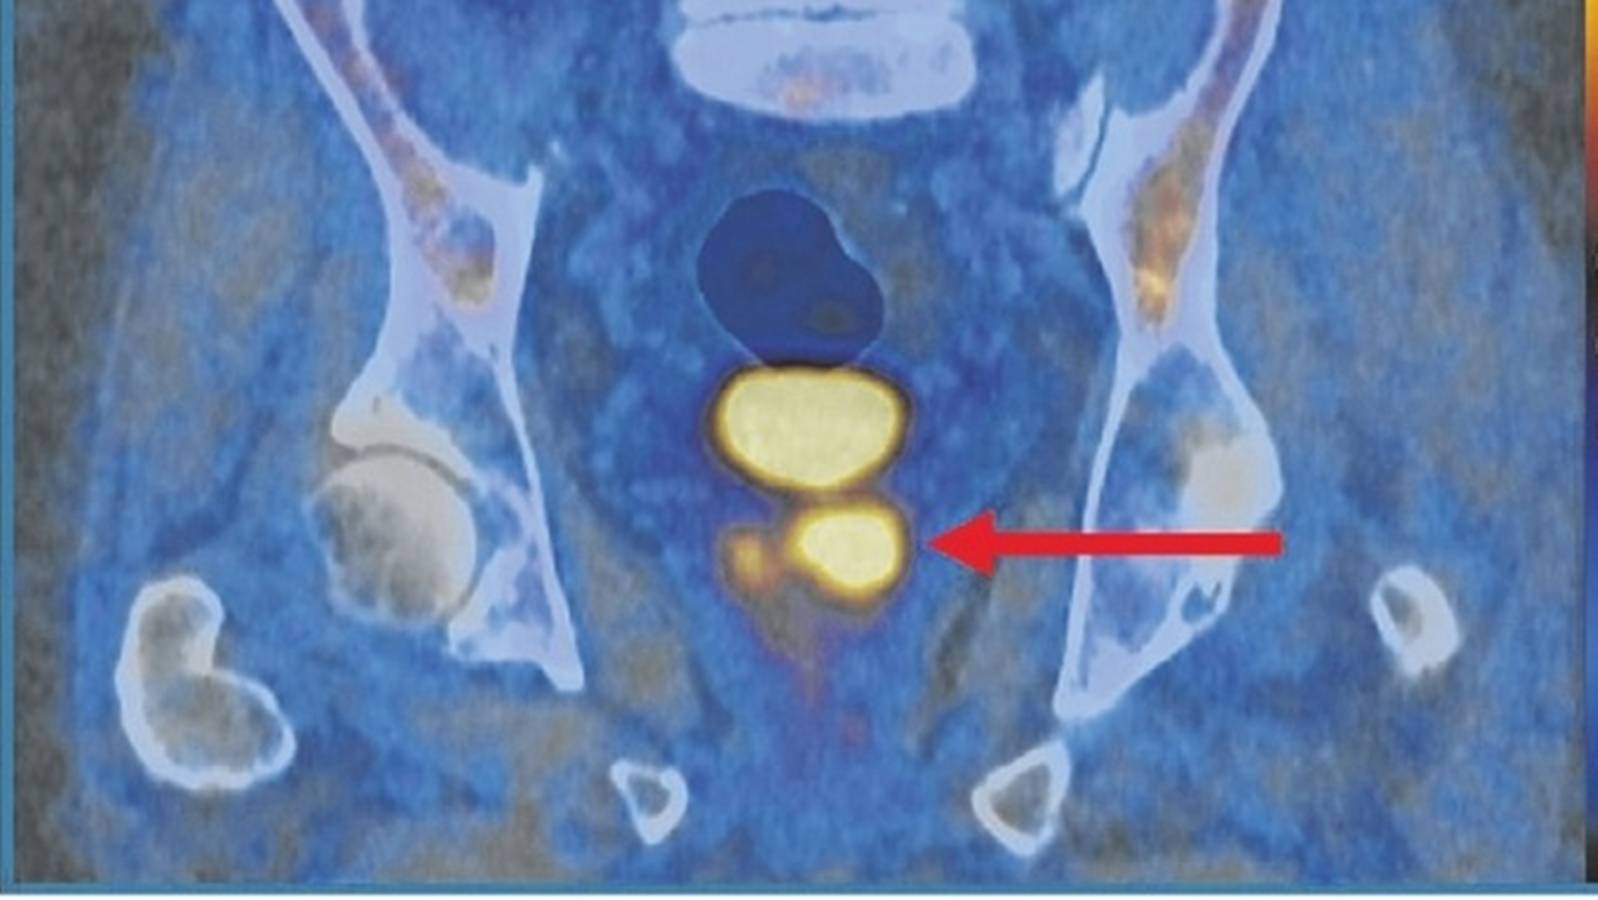

(Foto: Ensaio PRIMARY2)